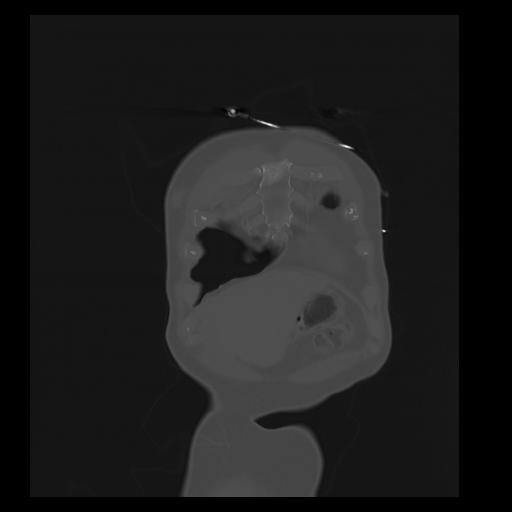

32 PULMON,CE,Coronal,3.000,PULMON,Coronal,